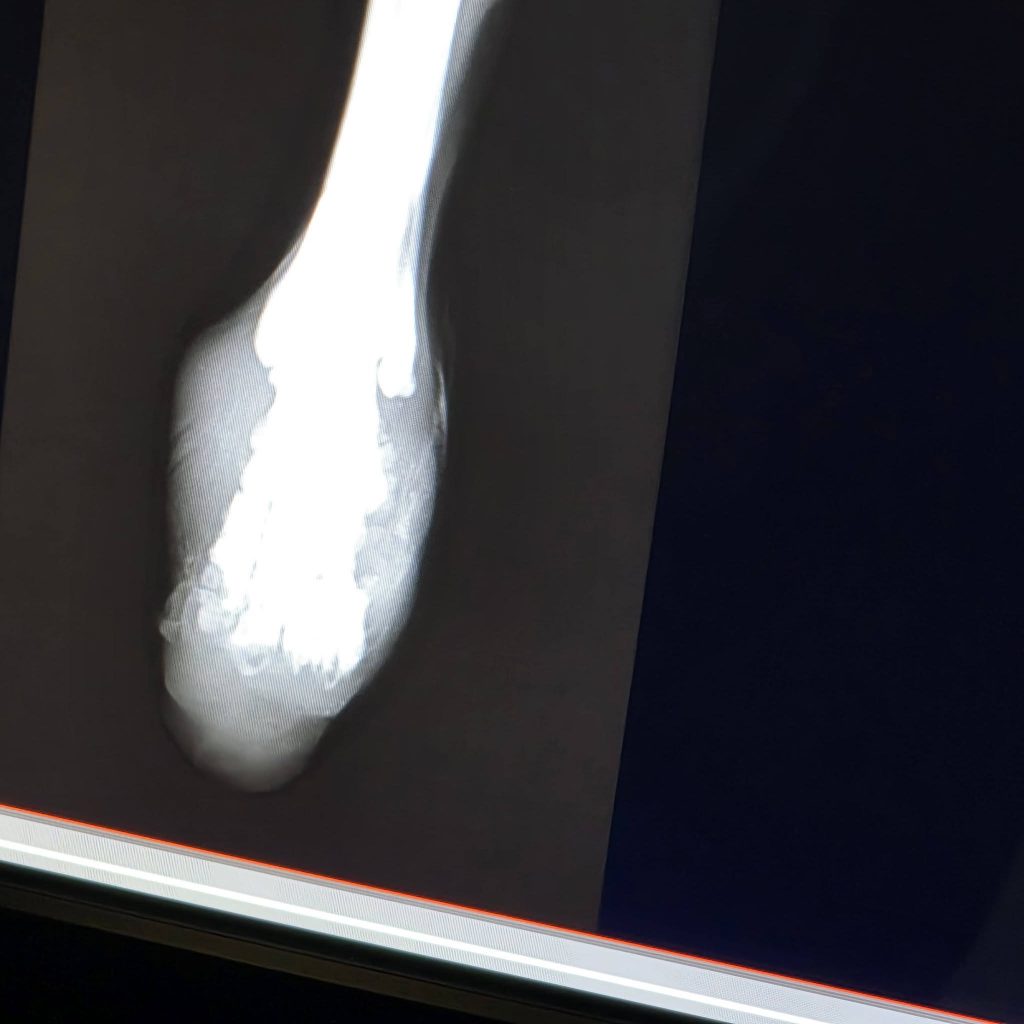

Sicher ist: Kein Zug hat ihm die Beine abgetrennt.

Die Verletzungen an beiden Hinterbeinen sind nicht zur gleichen Zeit entstanden. Es ist leider sehr wahrscheinlich, dass sie absichtlich verursacht wurden – unser Verdacht geht in Richtung einer Drahtschlinge.

Vor einigen ist unsere ungarische Tierschutzkollegin Betty schließlich zu ihm gefahren und hat ihn ins Krankenhaus gebracht, wo er sofort behandelt wurde. Einer der Stümpfe ist sogar auf dem Parkplatz der Klinik abgefallen, als er aus dem Auto gehoben wurde.